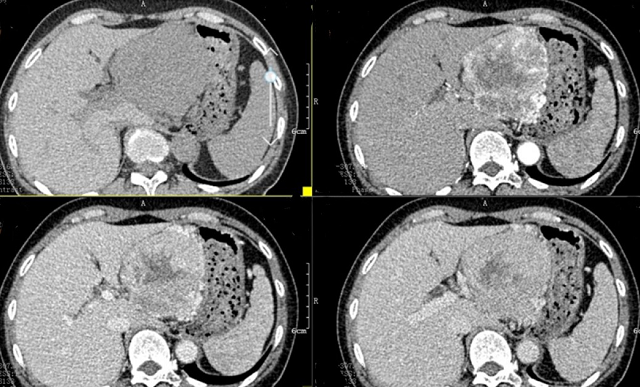

上腹部CT顯示胰腺巨大腫瘤

入院后,根據(jù)王女士病情,曹利平教授及其團(tuán)隊為她制定一套詳盡的術(shù)前檢查和治療方案。首先,安排做上腹部增強(qiáng)CT,并建議其先穿刺活檢明確病理。

“CT表現(xiàn)符合胰腺神經(jīng)內(nèi)分泌腫瘤,穿刺也證實無誤,但是瘤體實在太大,直徑約12cm左右,腹腔內(nèi)的門靜脈、腸系膜上靜脈、脾靜脈以及腹腔干這些重要血管統(tǒng)統(tǒng)包繞進(jìn)去了,且與周圍結(jié)腸系膜也有累及。”

曹利平教授帶著團(tuán)隊成員逐一分析,隱藏在瘤體附近的血管就像埋在炸彈旁的導(dǎo)火索,稍有不慎,便會引爆這顆瘤體炸彈,要想把腫瘤完整切除,更是難上加難。